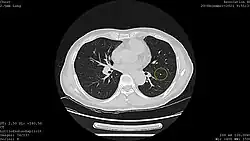

![]() Computed tomography (CT) scanner, a commonly recommended screening technique | |

Results from large randomized studies have recently prompted a large number of professional organizations and governmental agencies in the U.S. to now recommend lung cancer screening in select populations. The 3 main types of lung cancer screening are low-dose, computerized tomographic (LDCT) screening, chest x-rays, and sputum cytology tests.[4] Currently multiple professional organizations, as well as the United States Preventive Services Task Force (USPSTF), the Centers for Medicare and Medicaid Services (CMS) and the European Commission's science advisors[5] concur and endorse low-dose, computerized tomographic screening for individuals at high-risk of lung cancer.